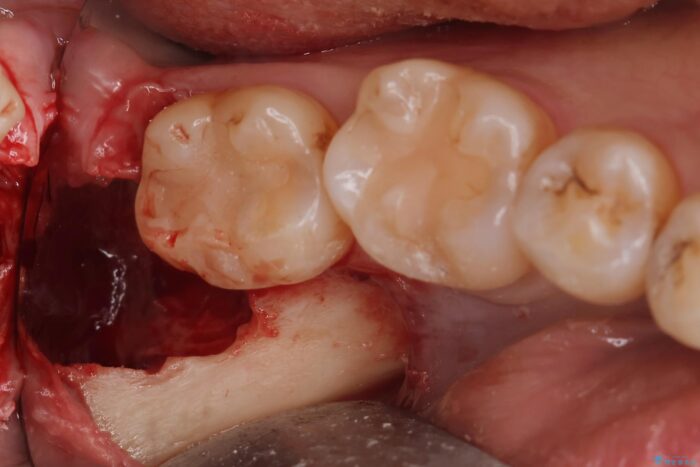

埋伏歯の抜歯

埋まっている親知らずを抜歯したいとご来院されました。

パノラマ,CT撮影を行い安全なことを確認して抜歯を行いました。

当日の抜歯も可能で、抜歯後1週間後に抜糸と消毒を行い処置は完了になります。